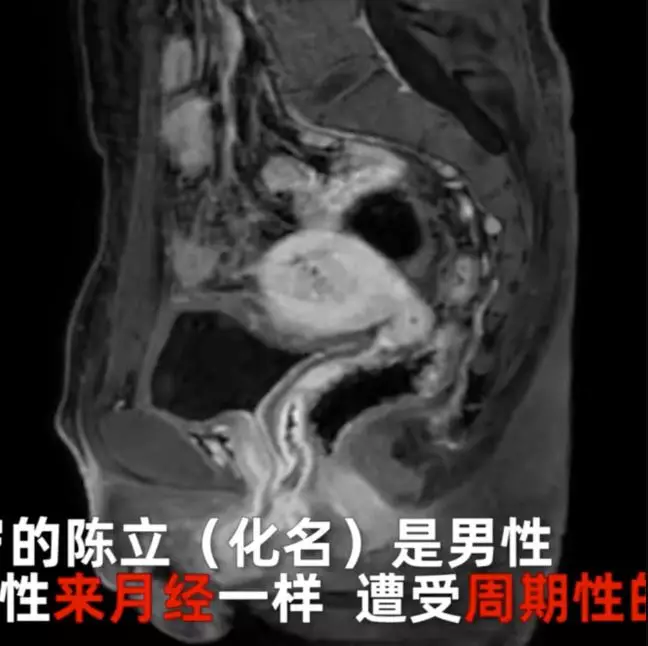

Semua bermula ketika Chen Li (nama samaran) menjalani operasi untuk memperbaiki keluhan buang air kecil yang tidak teratur selama masa pubertas. Sejak saat itu, selama lebih 20 tahun, pria asal Sichuan, Cina mengalami pendarahan ketika buang air kecil.

Selama mengalami buang air kecil dengan darah, Chen juga merasakan ketidaknyamanan pada perutnya selama lebih dari 4 jam. Pada saat itu dokter mendiagnosisnya dengan radang usus buntu. Akan tetapi kondisinya tidak membaik dan gejalanya berlanjut.